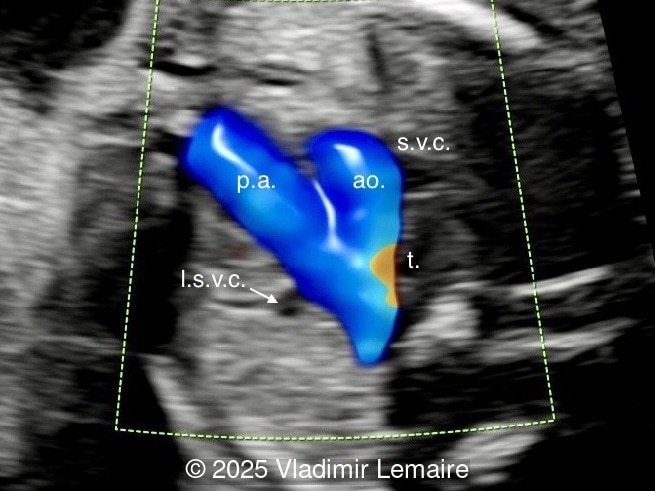

We present a case of isolated tricuspid atresia type 1 with persistent left superior vena cava. No other extracardiac anomalies were found. Our diagnosis was confirmed after birth.

In the images below, the abbreviations are as follows: RA: right atrium; RV: right ventricle; LV: left ventricle; MV: mitral valve; LA: left atrium; FO: foramen ovale; SVC: superior vena cava; LSVC: left superior vena cava; PV: pulmonary veins; PA: pulmonary artery; MPA: main pulmonary artery; RPA: right pulmonary artery; AO: aorta; dAO: descending aorta; aAO: ascending aorta; DA: ductus arteriosus; T: trachea; * marks the ventricular septal defect.

Color Doppler confirms the diagnosis on grayscale ultrasound, as it demonstrates the lack of blood flow across the tricuspid valve and a patent mitral valve. Due to increased blood flow across the mitral valve, aliasing is typically noted on color Doppler. Mitral valve regurgitation has been associated with a poor outcome. The right ventricular cavity is filled in late diastole from the left ventricle, through the ventricular septal defect. Left-to-right shunting across the ventricular septal defect can be seen on color Doppler. Color Doppler is helpful in the evaluation of flow across the great arteries. Flow across the pulmonary artery is generally antegrade. Pulmonary stenosis should be suspected when the vessel is diminutive in size rather than the demonstration of turbulent flow on color Doppler, which is typically absent in these cases.

Flow across the ductus arteriosus is usually antegrade. The demonstration of retrograde flow in the arterial duct is a sign of ductal-dependent pulmonary circulation with possible cyanosis in the newborn. Ductal-dependent pulmonary circulation in tricuspid atresia is seen in severe pulmonary stenosis or atresia in association with a small right ventricle.

Associated cardiac findings include a large interatrial communication such as a patent foramen ovale or an atrial septal defect, transposition of the great arteries, and various degrees of ventricular outflow obstruction. Ventricular outflow obstruction can vary from patent pulmonary artery to stenosis and atresia, and from patent aortic arch to aortic stenosis, coarctation, or interruption of the aortic arch. Other associated cardiac lesions include persistent left superior vena cava as presented in this case, right aortic arch, pulmonary venous abnormalities, and juxtaposition of the atrial appendages. Extracardiac anomalies can be found in tricuspid atresia and there is a rare association with chromosomal aberration such as microdeletion 22q11. Fetal karyotyping should be offered.